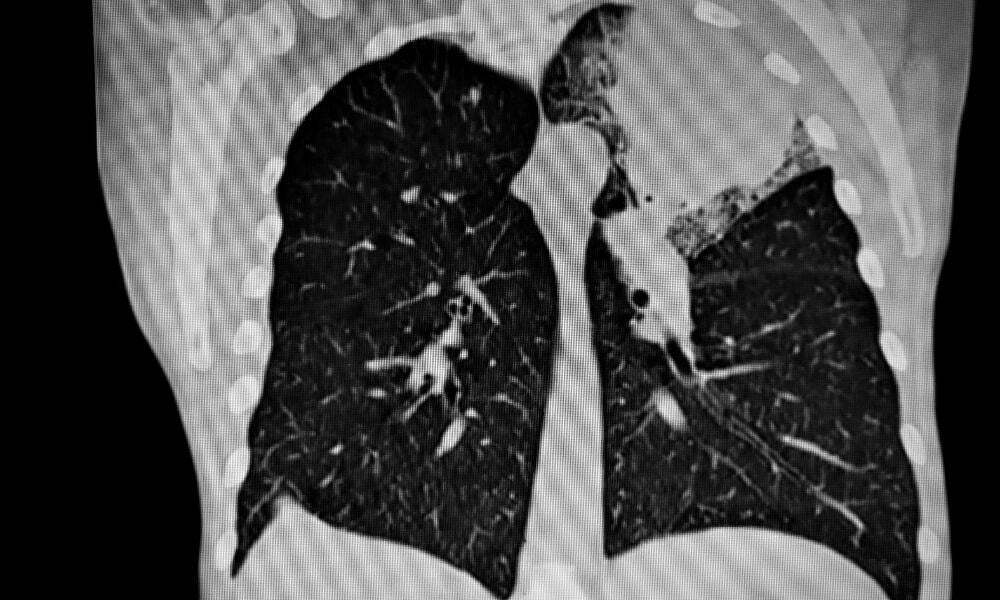

Bir kişi ağzından veya burnundan nefes alamıyorsa, doktor cerrahi bir hava yolu oluşturabilir. Bazen, bir kişi muhtemelen trakeadaki bir yaralanma veya tıkanıklık nedeniyle akciğerlere daha az hava akışı yaşayabilir. Akciğer fonksiyonunu veya kan oksijenlenmesini etkileyen tıbbi bir durumun bir sonucu olarak da ortaya çıkabilir. Sebep ne olursa olsun, bir trakeostomi, bir kişinin nefes almasına yardımcı olabilir. Bir trakeostomi, boynun önündeki trakeaya bir açıklığın kesilmesini içerir. Doktor daha sonra açıklığa bir tüp sokar, böylece geçici veya kalıcı bir cerrahi hava yolu oluşturur. Bazı insanlar tüp yoluyla kendi kendine nefes alabilirler. Diğer durumlarda, bir doktorun tüpü bir ventilatöre veya solunum makinesine bağlaması gerekebilir.

- Göğüs duvarı ve akciğerler (pnömotoraks) arasında hava birikmesi, bu da ağrıya, solunum problemlerine veya akciğer çökmesine neden olur